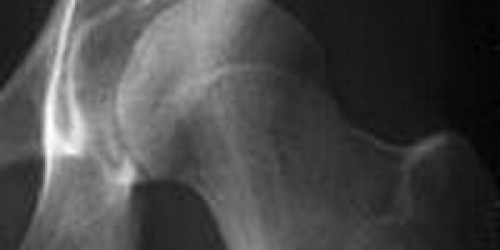

hi I am a male 41 yrs for the past two months I have been experiencing pain on left bottom side of my hip and been urinating constantly I get the pain mostly when driving or walking to much I don't drink or smoke and I don't left hevy things please help thks

Hi, pain in left side lower abdomen is generally associated with the urinary incontinency with considering your age   may be due to some prostrate problem or urinary bladder problem. Did you have any other complaints of nausea, vomiting? If urinary incontinency is observed in this two month only without any medical history I like to suggest you consult any urologist or go for USG pelvis.